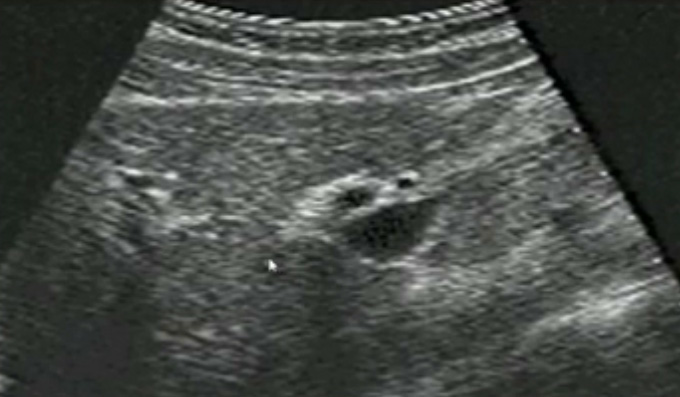

膽囊的位置、形態(tài)、大小、壁厚,內(nèi)部及附壁是否有異?;芈?尤其膽囊要注意頸部,還要看有沒慢性炎癥的征象,腫瘤或隆起樣病變.正常膽囊聲像圖是像個(gè)瓣,膽囊正常大小,頸部指向肝門膽囊輪廓清晰,壁薄很光滑呈線狀,囊內(nèi)無(wú)回聲,后壁回聲增強(qiáng)。為什么無(wú)回聲呢?因?yàn)槟懼且后w,水,血液這些都是無(wú)回聲的。膽囊頸和門靜脈或門脈右支根部之間有一線狀高回聲帶連結(jié),這是識(shí)別膽囊位置的重要標(biāo)志。膽囊長(zhǎng)徑一般不超90mm;前后徑2030mm,不超過(guò)40m正常充盈膽囊壁厚<3mm。 膽囊皺褶非常常見,